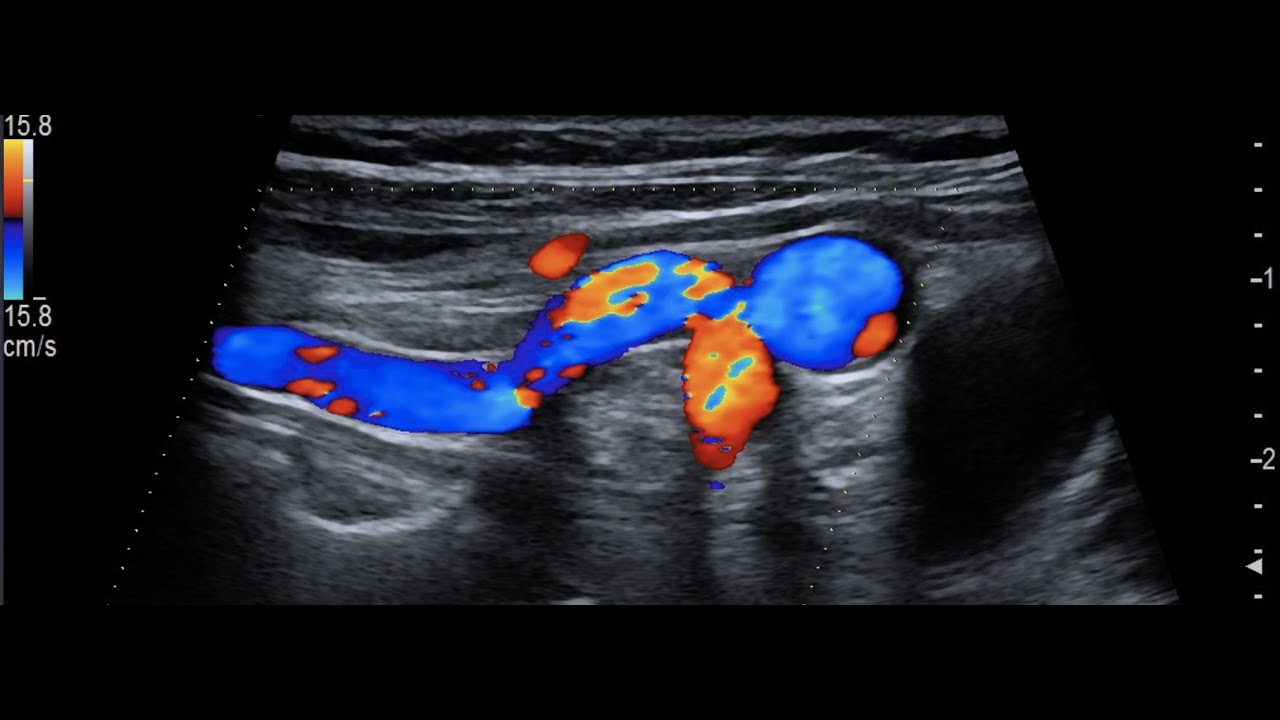

Видео узи артерий

Видео узи артерий 107 фото